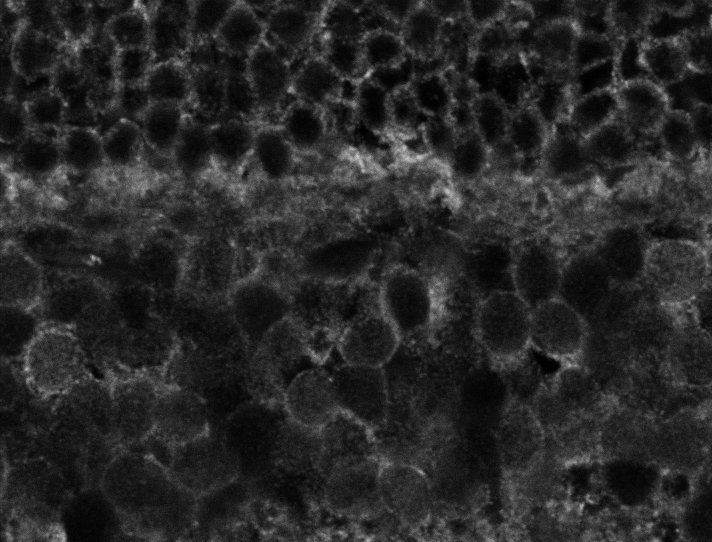

Healthy Choroid